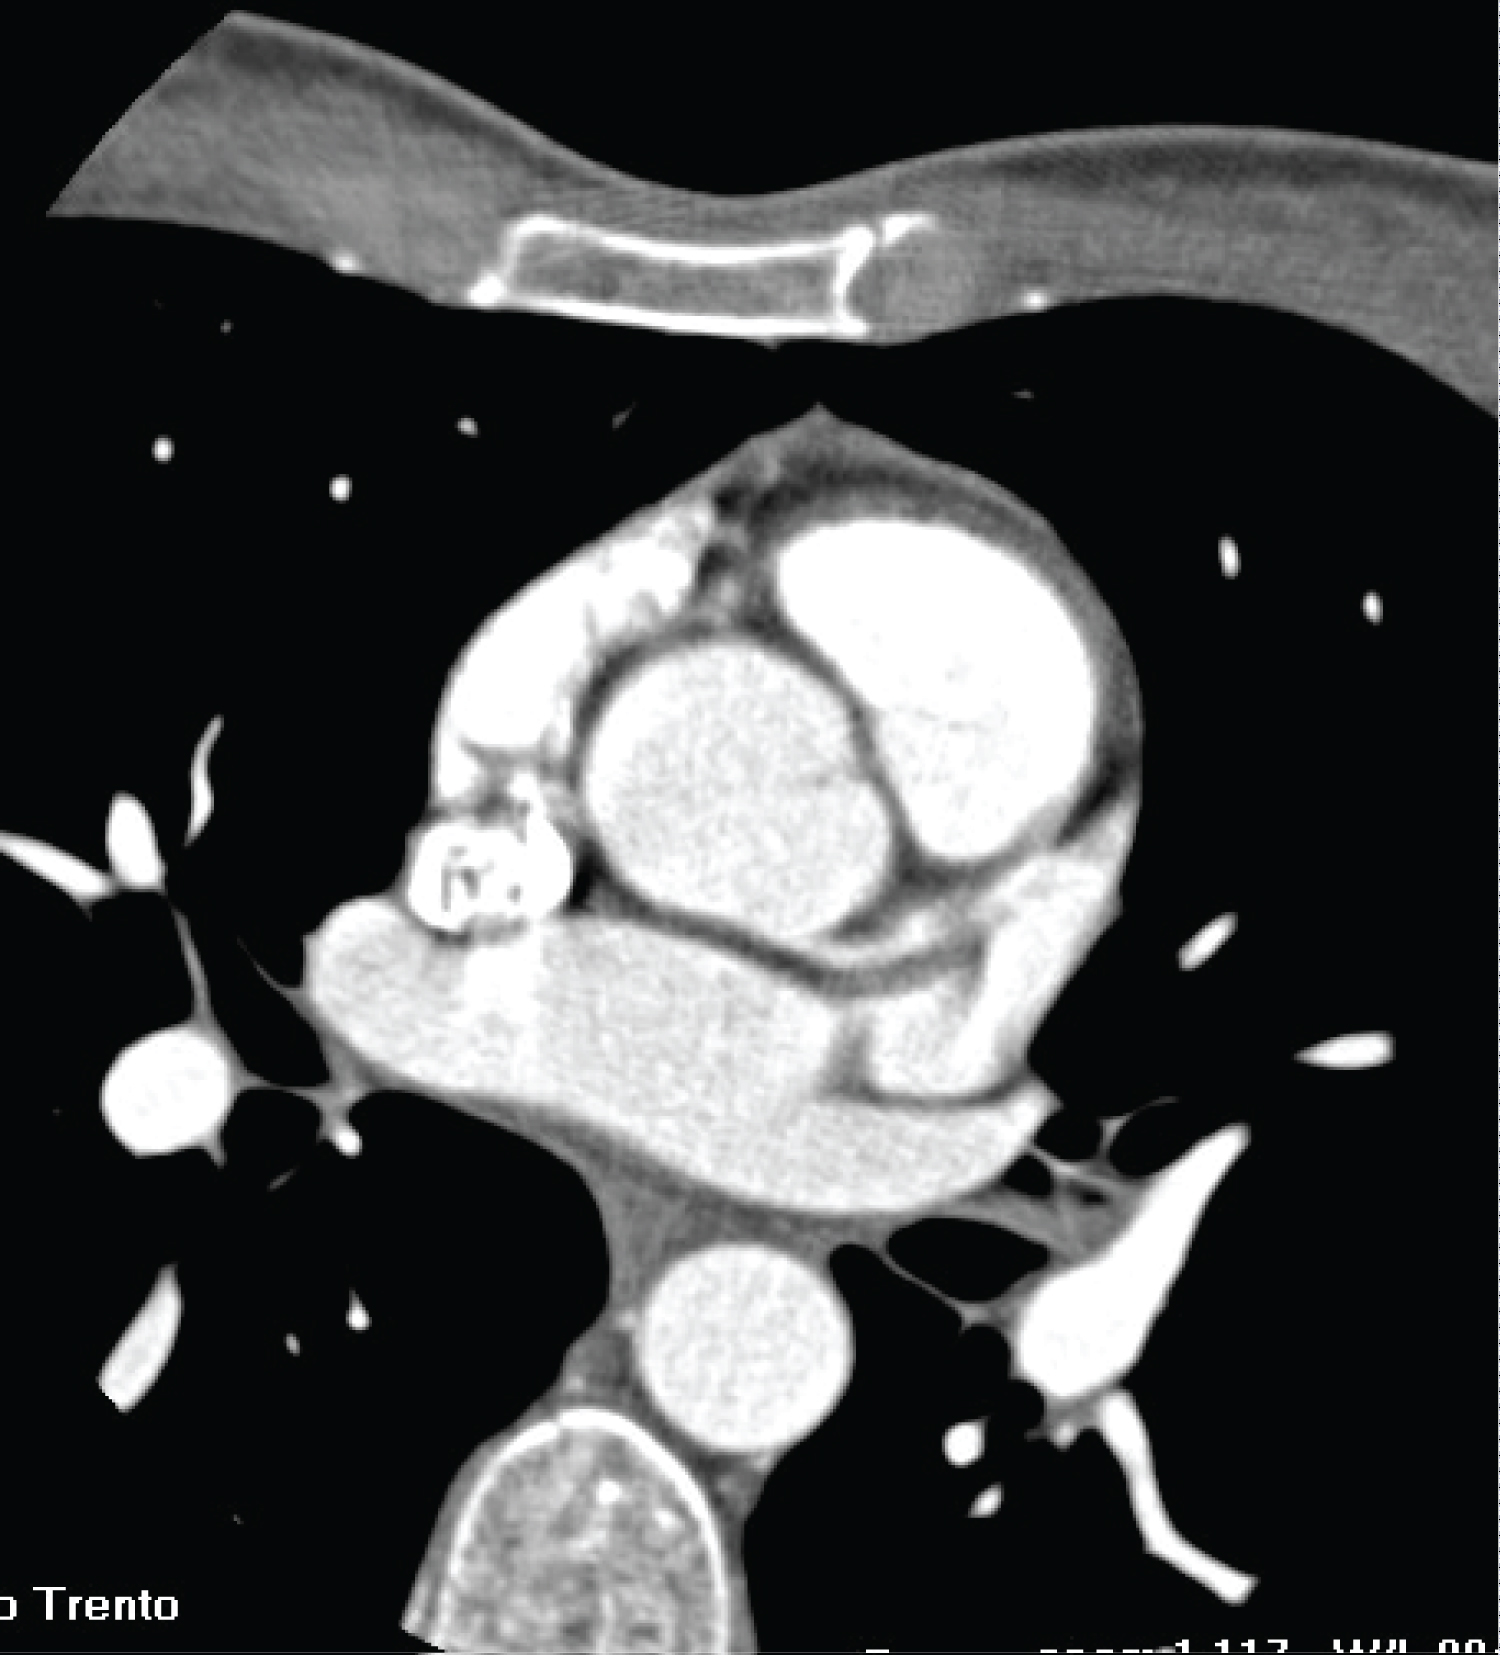

In 2015 (age 19 years old) a coronary CT (Figure 8 and Figure 9) showed persistence of the aneurysm, which was moreover increased in diameter (8 mm). Another aneurysm was also evident in the medium segment of the RCA, smaller than the previous one, measuring 4.2 mm of diameter and 16 mm of length.

Figure 8 and 9: 3D-CCTA showing the aneurysm in the proximal portion of the RCA. View Figure 8 and 9